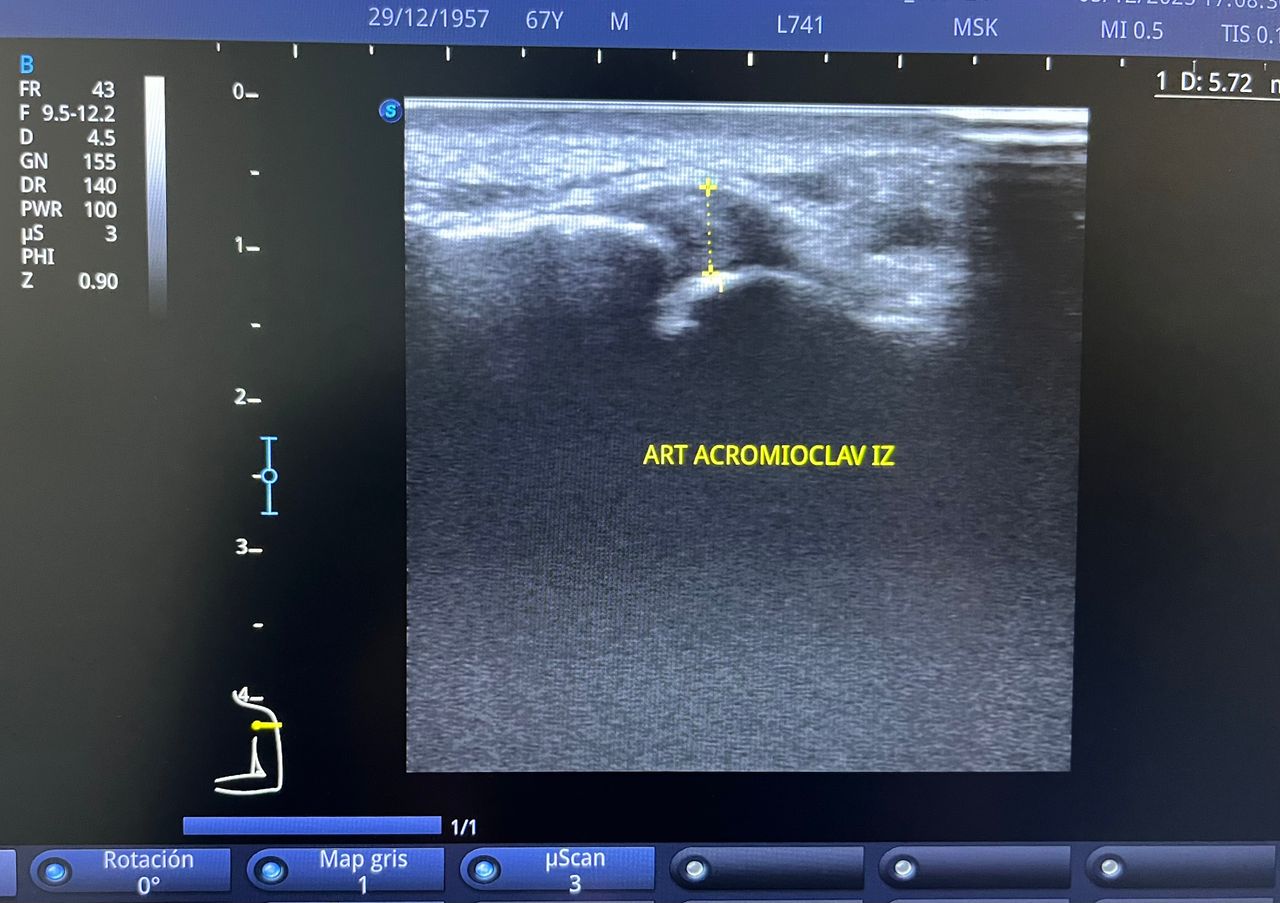

Médico general con 15 años de experiencia, master en enfermedades infecciosas y antibioticoterapia por parte de la Universidad Cardenal Herrera en Valencia, ademas de diversos diplomados en el área de Infectología y Parasitología, Urgencias, Imagenología y Medicina del Trabajo. He laborado en Hospitales y Clínicas en el área de Urgencias, en Laboratorios realizando estudios de Imagen, en especifico ultrasonidos de todo tipo desde básicos hasta avanzados incluidos los obstétricos estructurales, en Secretaría de Salud del Estado de Querétaro realizando ultrasonidos obstétricos para la detección de malformaciones en los tres trimestres del embarazo en diversos centros de salud, como médico de Empresas en el campo de Salud Laboral y actualmente en este consultorio en donde para su mejor atención y siempre buscando integrar la mayoría de las herramientas diagnosticas cuento con equipo de ultrasonido como apoyo en la exploración del paciente o como servicio diagnostico por imagen, realizo ultrasonidos convencionales (hepatobiliar (hígado, páncreas, vesícula y bazo), vías urinarias, ginecológico abdominal y transvaginal, tiroideo, prostático, testicular, pared abdominal) y especializados (dopler obstétrico en los 3 trimestres de embarazo), musculoesquelético en lesiones deportivas. También cuento con un equipo de electrocardiograma de 12 derivaciones para monitoreo completo del funcionamiento cardiaco, espirometria para evaluar la función pulmonar en la consulta, pruebas rápidas que se realizan en consultorio para detectar de forma mas precisa enfermedades infecciosas como Influenza A y B, covid19, infecciones urinarias, dengue, zika, chikungunya. Cuento con diversas vacunas para prevención de enfermedades. Siempre con el objetivo de dar el mejor servicio y atención a su salud. Lo espero en consulta para escucharlo y estudiar su caso de la forma más completa posible, estoy seguro de que tendremos las mejores opciones para su tratamiento. Mi tranquilidad es que usted se vaya con todas sus preguntas e inquietudes resueltas.

• Ultrasonido diagnóstico